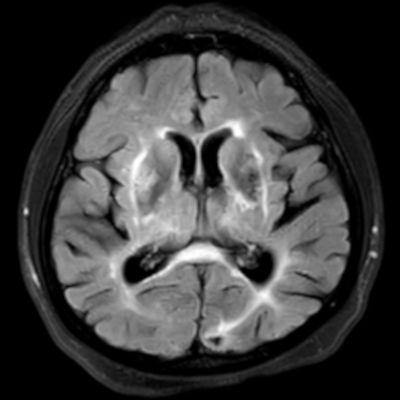

45 yaş, K

4 yıl önce akut sağ hemiparezi, konuşma bozukluğu ve dış merkezde serebellar iskemi tanısı ile ASA kullanımı öyküsü

Konuşma bozukluğu, yersiz gülme ve ağlama atakları, denge kaybı ve uyuşmaları devam ediyor

CADASIL

CADASIL SENDROMU